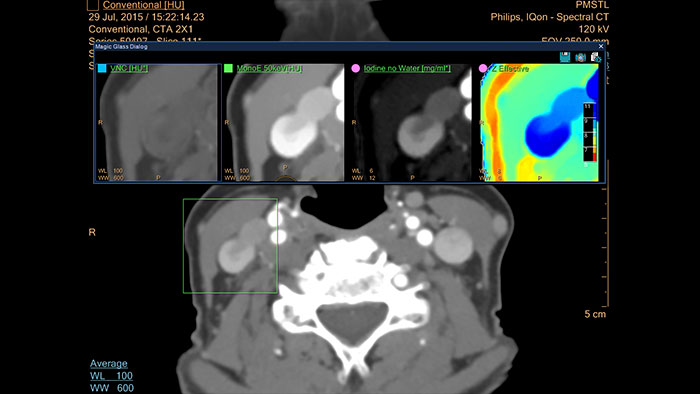

Spectral Magic Glass on PACS

CT Spectral Magic Glass on PACS*

IQon Spectral CT Functionality

IQon Spectral CT is the only scanner to offer CT Spectral Light Magic Glass and CT Spectral Magic Glass on PACS, helping radiologists review and analyze multiple layers of spectral data at once, including on their PACS.

spectral magic glass on pacs thumbnail

Benefits

• On-demand simultaneous analysis of multiple spectral results for an Region Of Interest (ROI).

• Integrates into a health system’s current PACS setup for certain PACS vendors.

• Spectral results viewable, during a routine reading.

• Enterprise-wide spectral viewing and analysis allows access to capabilities virtually anywhere in the organization.

* Standard with the CT Spectral option on IntelliSpace Portal.